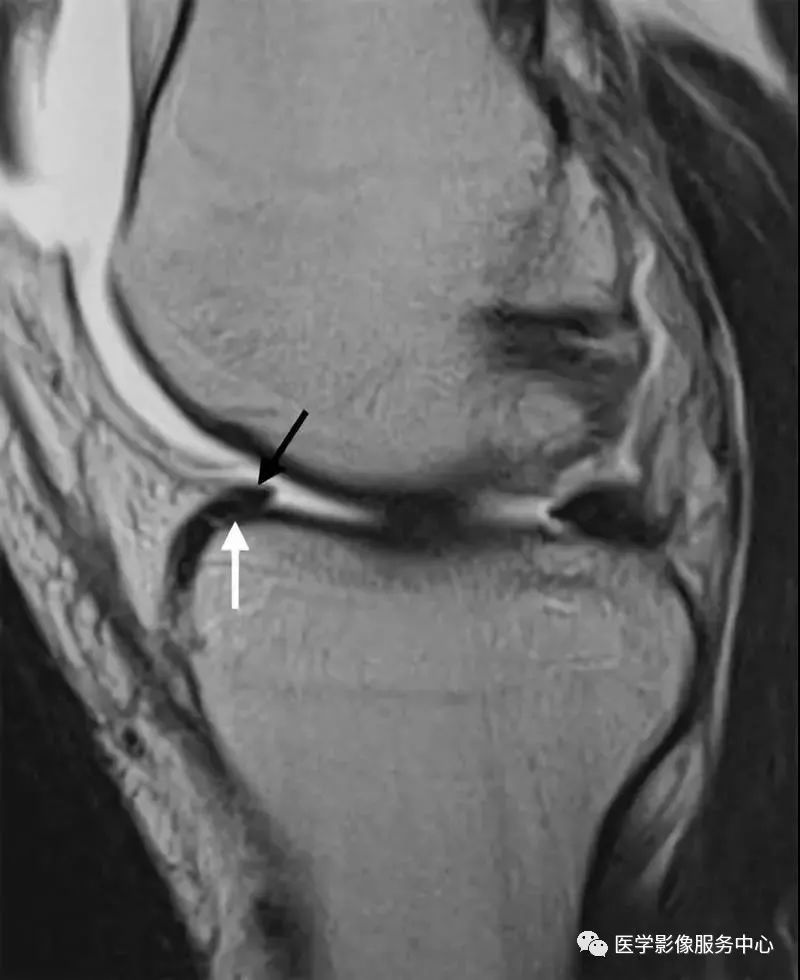

黑色箭头所指为半月板前角,白色箭头所指为撕裂的半月板向前移位